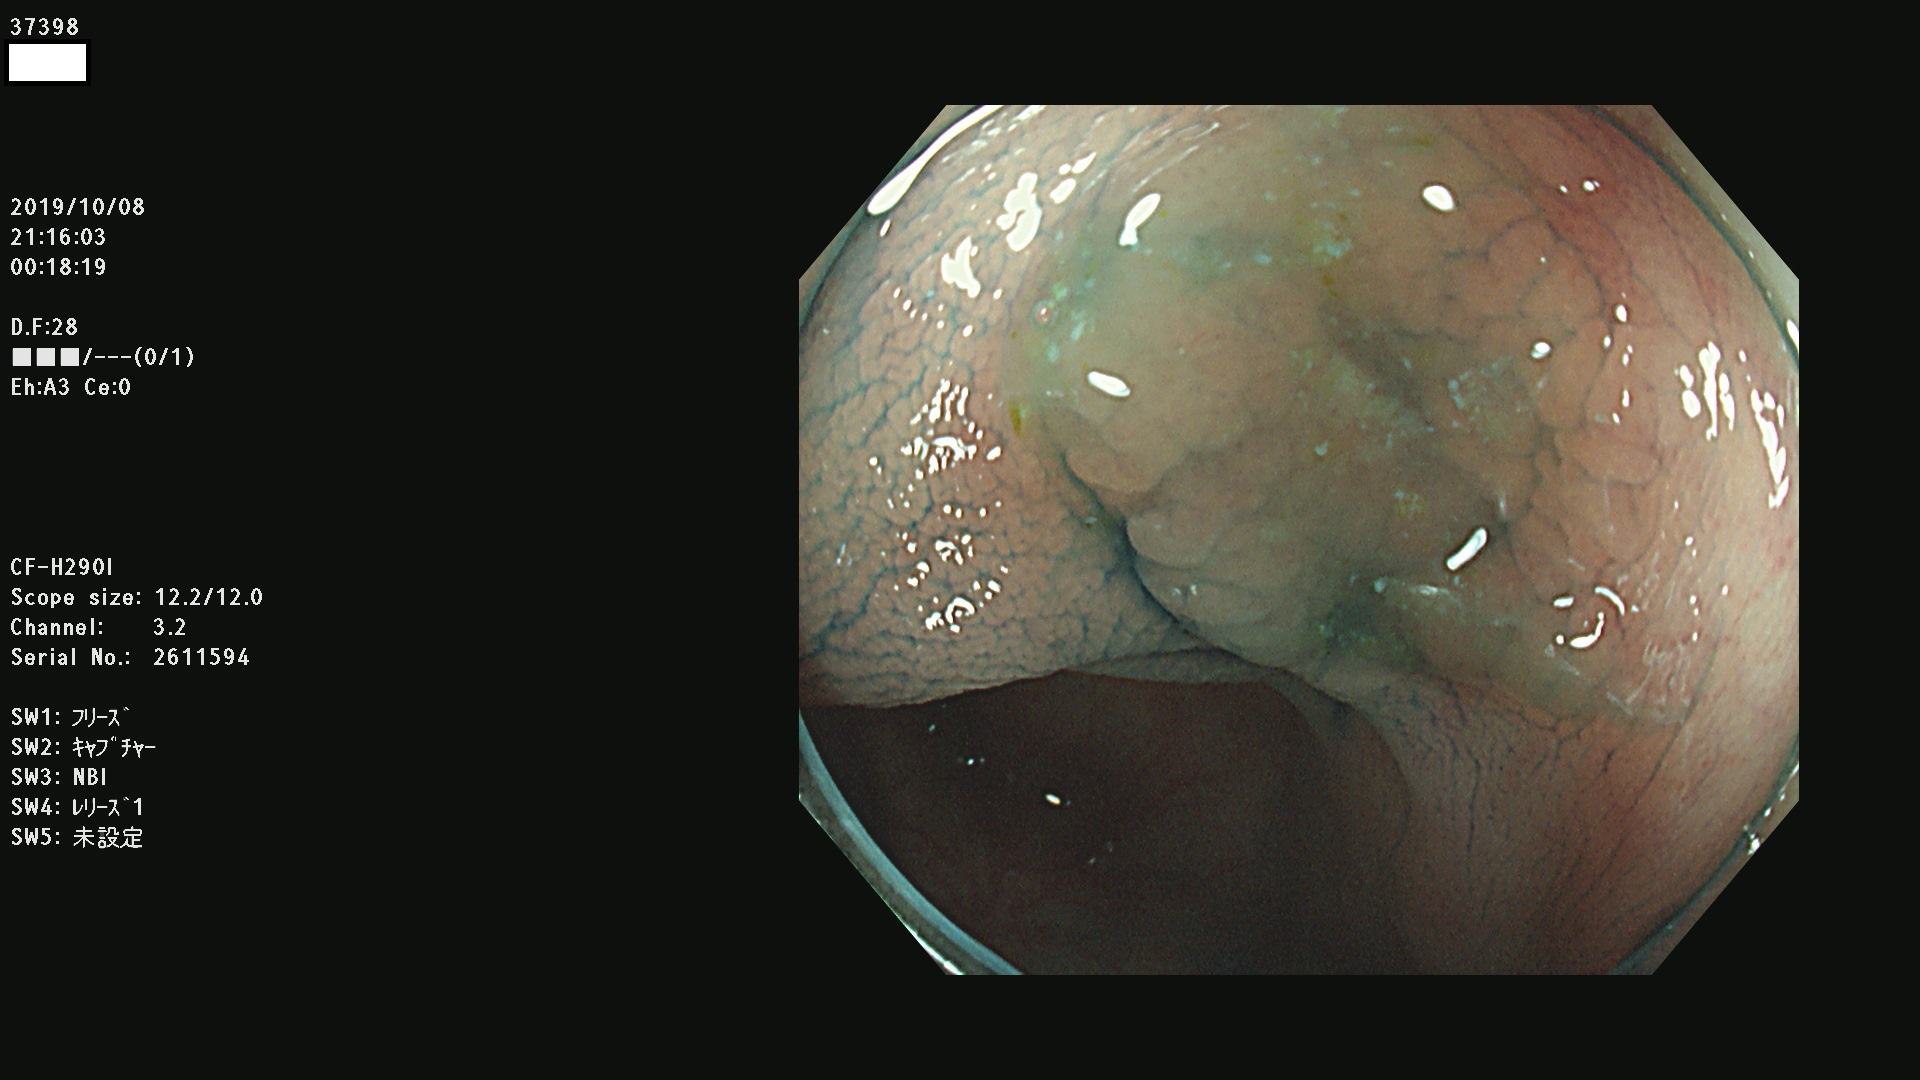

37300(SSAPのみ) 37301 37303 37304 37306 37307 37308 37309 37312 37313 37315(SSAPのみ) 37316 37317(SSAPのみ) 37319 37321(SSAPのみ) 37322 37323 37324 37325 37326 37328(SSAPのみ) 37329 37330 37331 37332(SSAPのみ) 37333 37334 37336 37337 37338 37340 37342 37343(SSAPのみ) 37344 37345 37346 37347 37348 37352(SSAPのみ) 37353 37354 37355 37356 37358 37360 37361(SSAPのみ) 37362 37363 37366 37367 37369 37370 37371 37372(SSAPのみ) 37375 37376 37377 37380 37381(SSAPのみ) 37382 37383 37384 37385(SSAPのみ) 37386 37387 37388 37389 37390 37392(SSAPのみ) 37393 37394 37395 37396(SSAPのみ) 37397 37398(SSAPのみ) 37399

発見困難で危険性の高い平坦型病変(上記100名より抽出) )